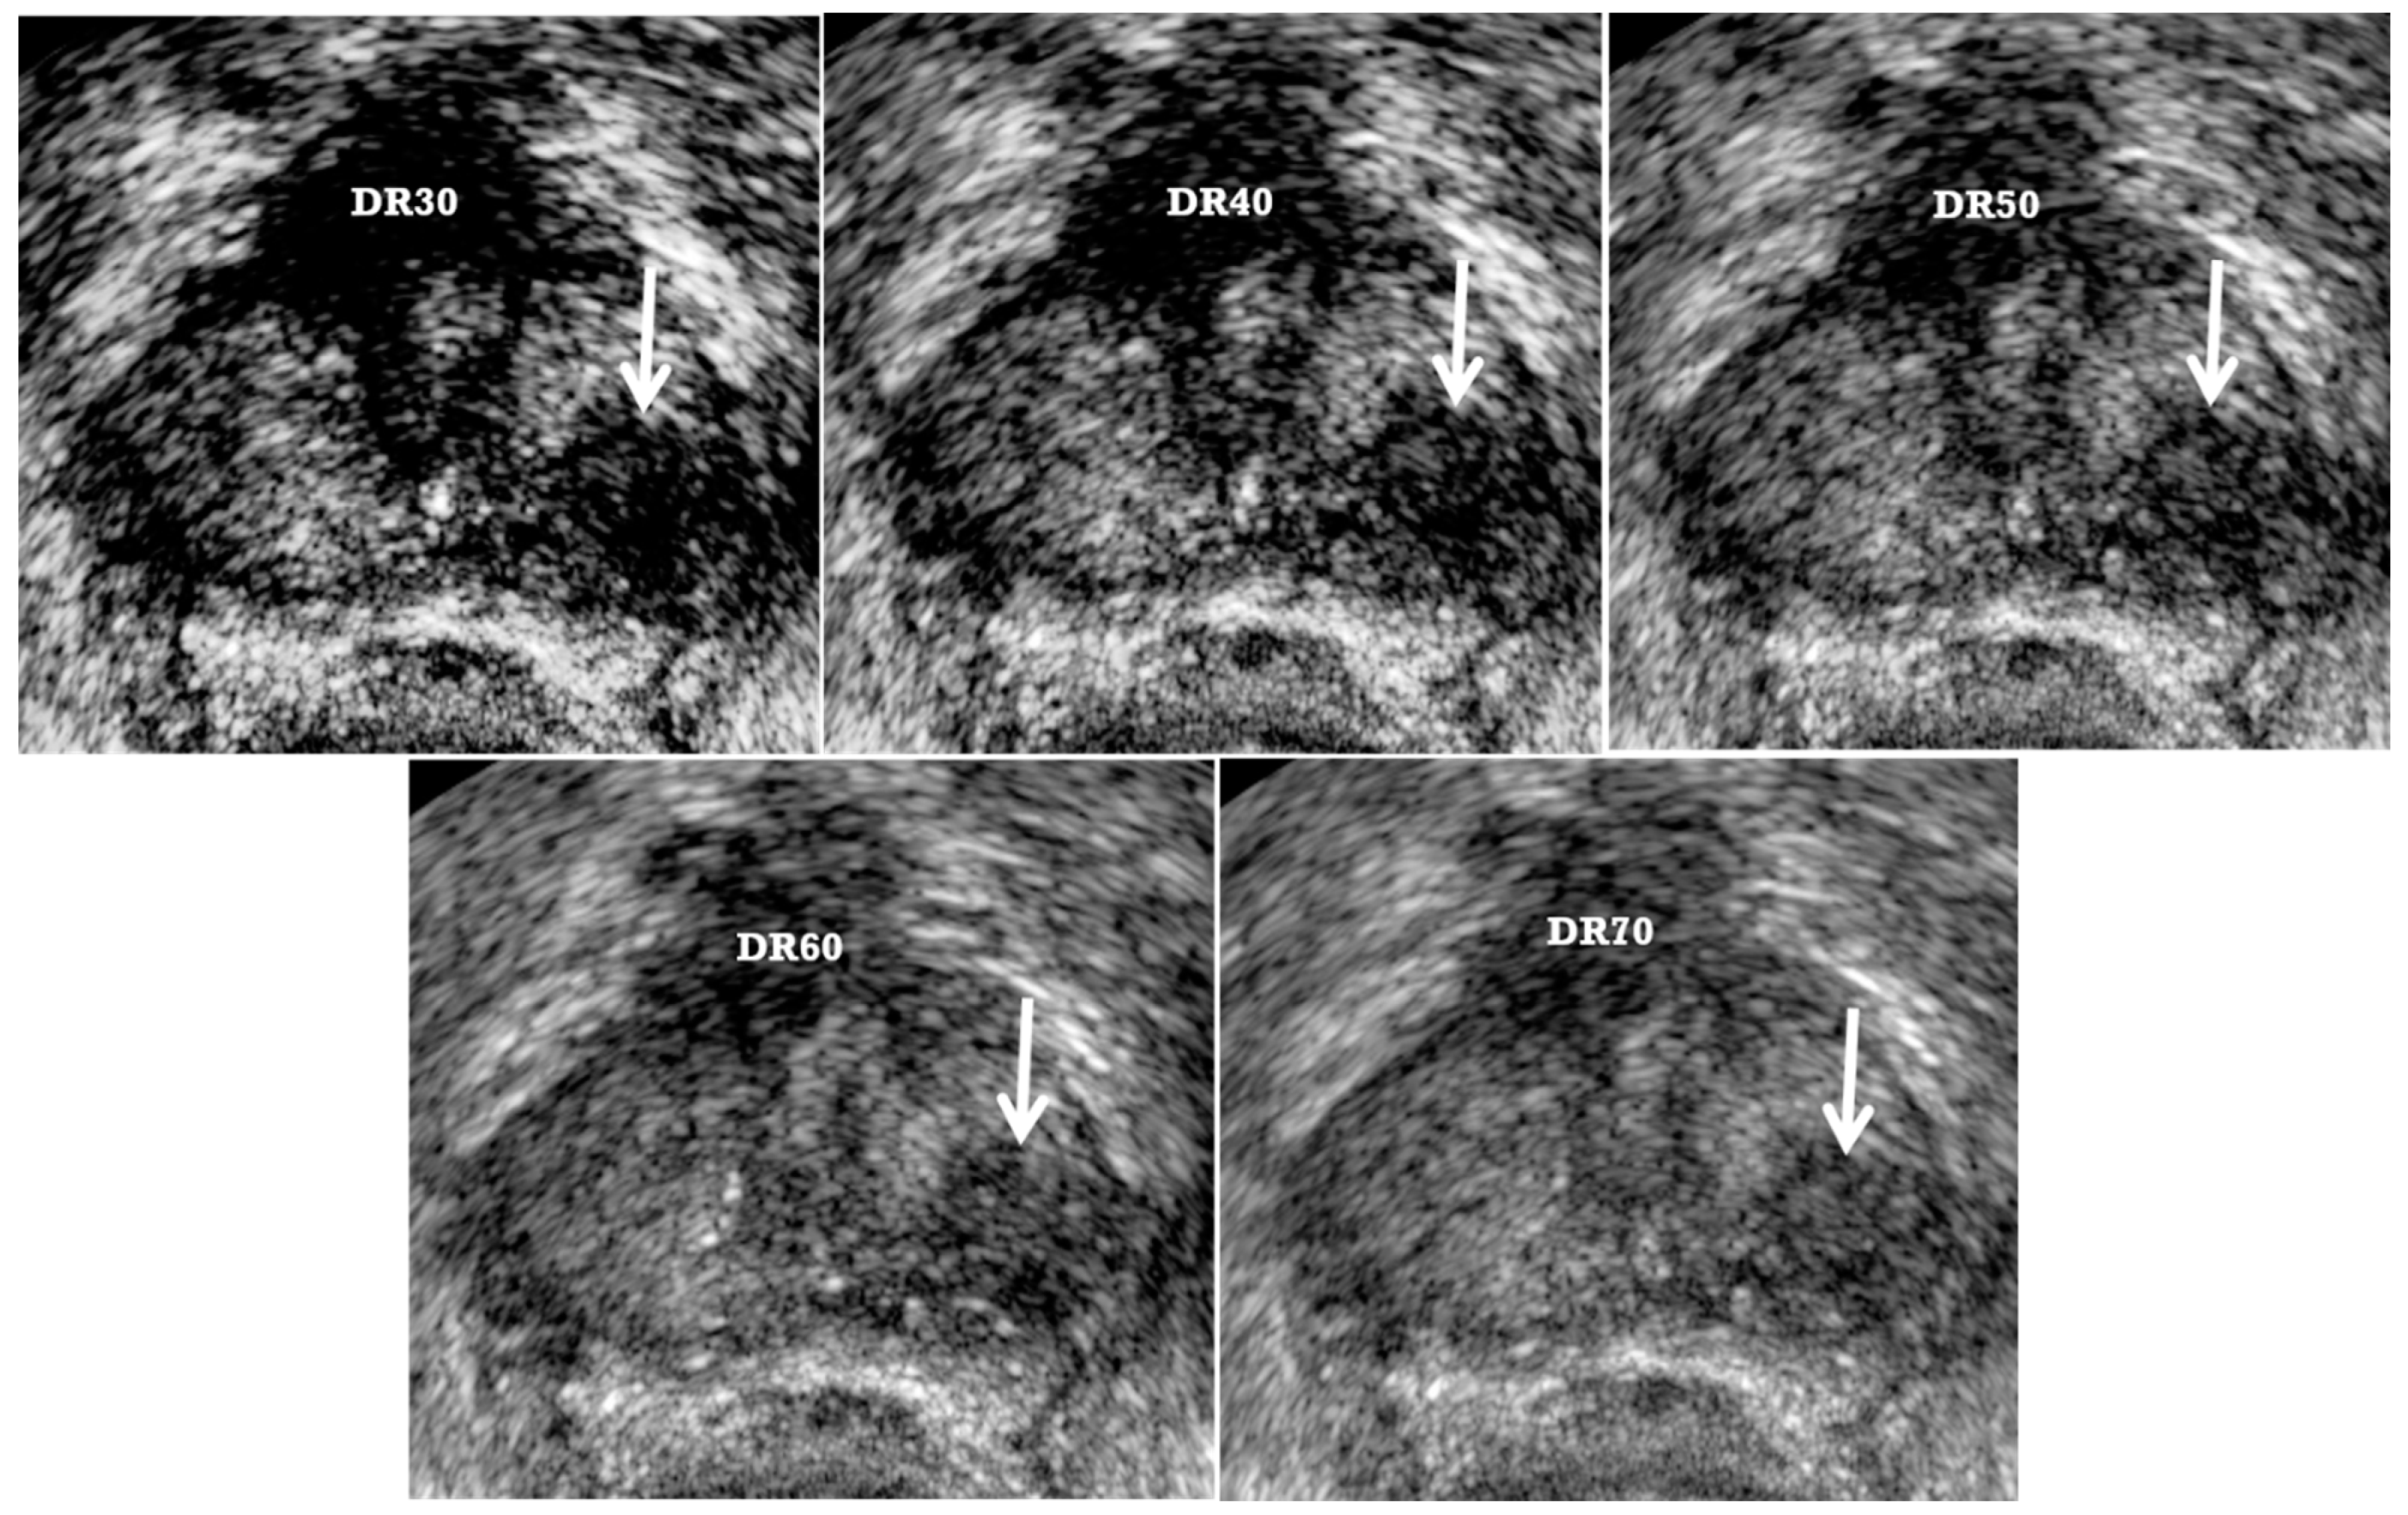

2. TRUS Imaging Protocols

| Dynamic range | High | Low |